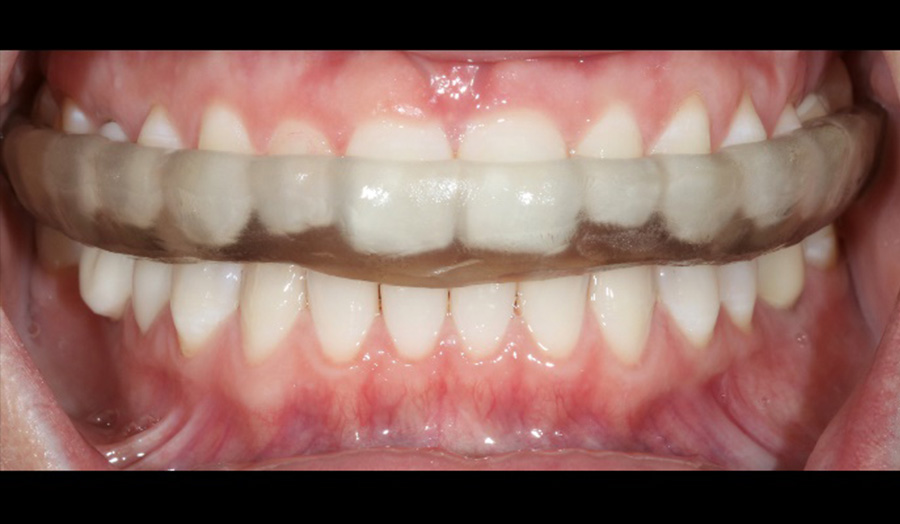

A 47-year-old female presented to my office with concerns about six anterior zirconia crowns recently done at another office. The efficiency and ease of use of the Primeprint Solution allows me to quickly print models on the same day of treatment which enables me to present a preview of treatment to patient before the final production with CEREC Primemill.

Before: Initial oral situation with significant asymmetry of the lips when smiling

Usage: 3D-printed model with ditched dies manufactured with Primeprint Model material

After: Final restoration